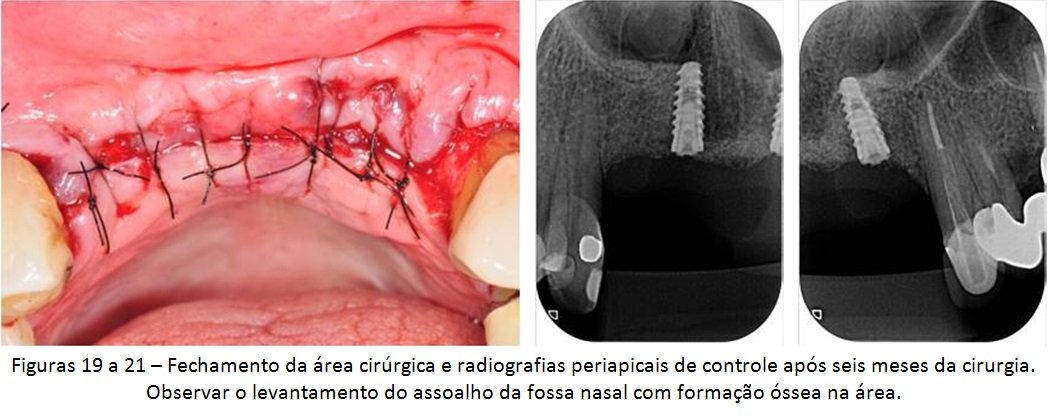

A paciente em questão foi diagnosticada com peri-implantite e recebeu tratamento cirúrgico para eliminação dos sinais e sintomas dessas alterações, mas a doença recorreu e ela acabou perdendo os implantes. A solução escolhida por nós foi o levantamento da cavidade nasal para possibilitar a colocação de dois novos implantes, viabilizando uma futura prótese fixa de quatro elementos. Veja a descrição detalhada do caso abaixo.

O levantamento do assoalho da fossa nasal, apesar de pouco divulgado, pode ser uma interessante solução para casos como esse descrito hoje. Obviamente que poderíamos ter adotado outros tipos de técnicas para se reabilitar a área. Contudo, qualquer outra alternativa teria sido muito mais invasiva, aumentando a morbidade e o tempo de tratamento. Mesmo sabendo que a prótese final será uma reabilitação “dento-gengival”, onde usaremos muita gengiva artificial, acreditamos que essa solução ainda é a melhor escolha em função de todo o histórico do caso e da paciente.